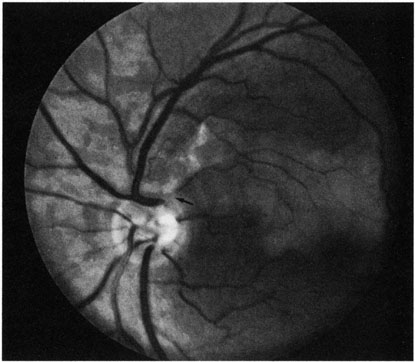

POSTERIOR CILIARY ARTERY OBSTRUCTION

Obstruction of one of the posterior ciliary arteries may result in a whitening of the area of the retina supplied by the involved posterior ciliary artery and the subsequent appearance of patchy pigmentation in the same area. However, in patients with anterior ischemic optic neuropathy secondary to temporal arteritis the retina may appear normal (Fig. 5). In the case of either the medial posterior ciliary artery or the lateral posterior ciliary artery, the area involved is the size of approximately half of the choroid.121–123 In the case of a long posterior ciliary artery, the temporal side of the eye including the macula is involved.121

Fig. 5. A: Ischemic optic neuropathy in a patient with giant cell arteritis. B and C: Intravenous fluorescein angiography demonstrates delayed filling of the lateral posterior ciliary artery.

We have seen several patients with anterior ischemic optic neuropathy with suspected temporal arteritis where the Westergren sedimentation rate and C-reactive protein were normal and the intravenous fluorescein angiogram helped confirm the diagnosis (Fig. 5).